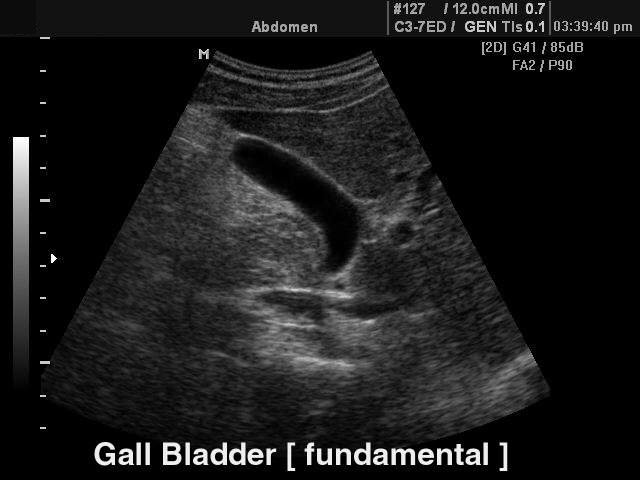

Конвексный датчик C 2-5EL/40/85

Акушерские исследования (плод, сердце плода), гинекология (матка, яичники), абдоминальные исследования (печень, желчный пузырь, поджелудочная железа, селезенка, глубокие сосуды), почки.

Биопсийный набор: есть.

Конвексный датчик C 3-7ED/50/70